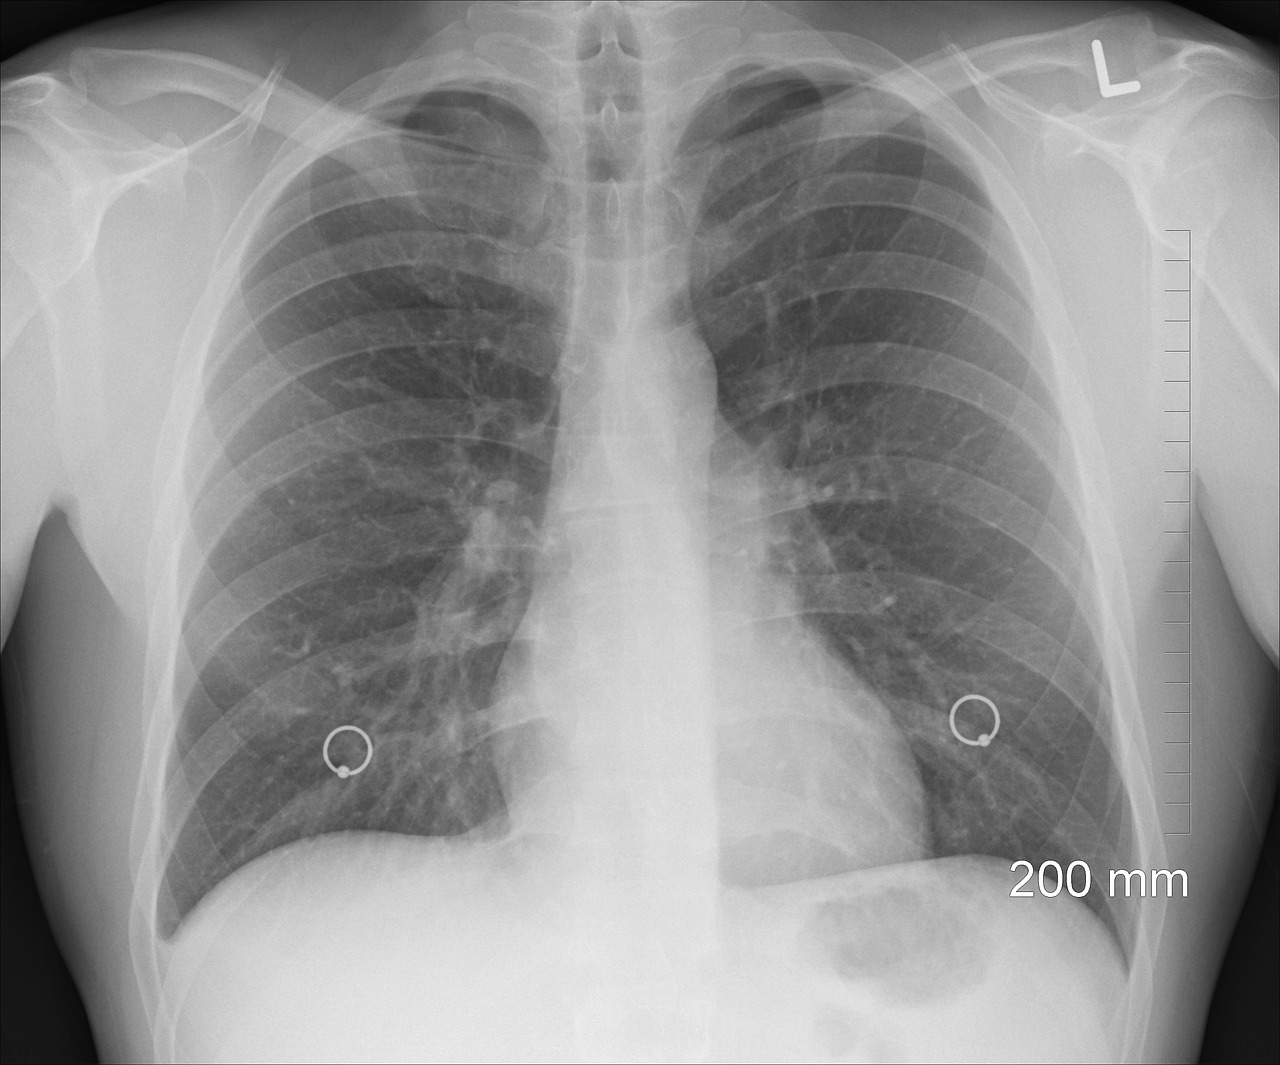

Se necessario, per escludere altre possibili cause, il medico potrebbe consigliare anche esami più approfonditi, come una radiografia del torace (utile per valutare il grado di infiammazione dei polmoni), un esame dell’espettorato (per scoprire quale agente sta causando la polmonite), una TC toracica (può mostrare la porzione di polmoni colpiti dalla malattia) e delle analisi del sangue complete.